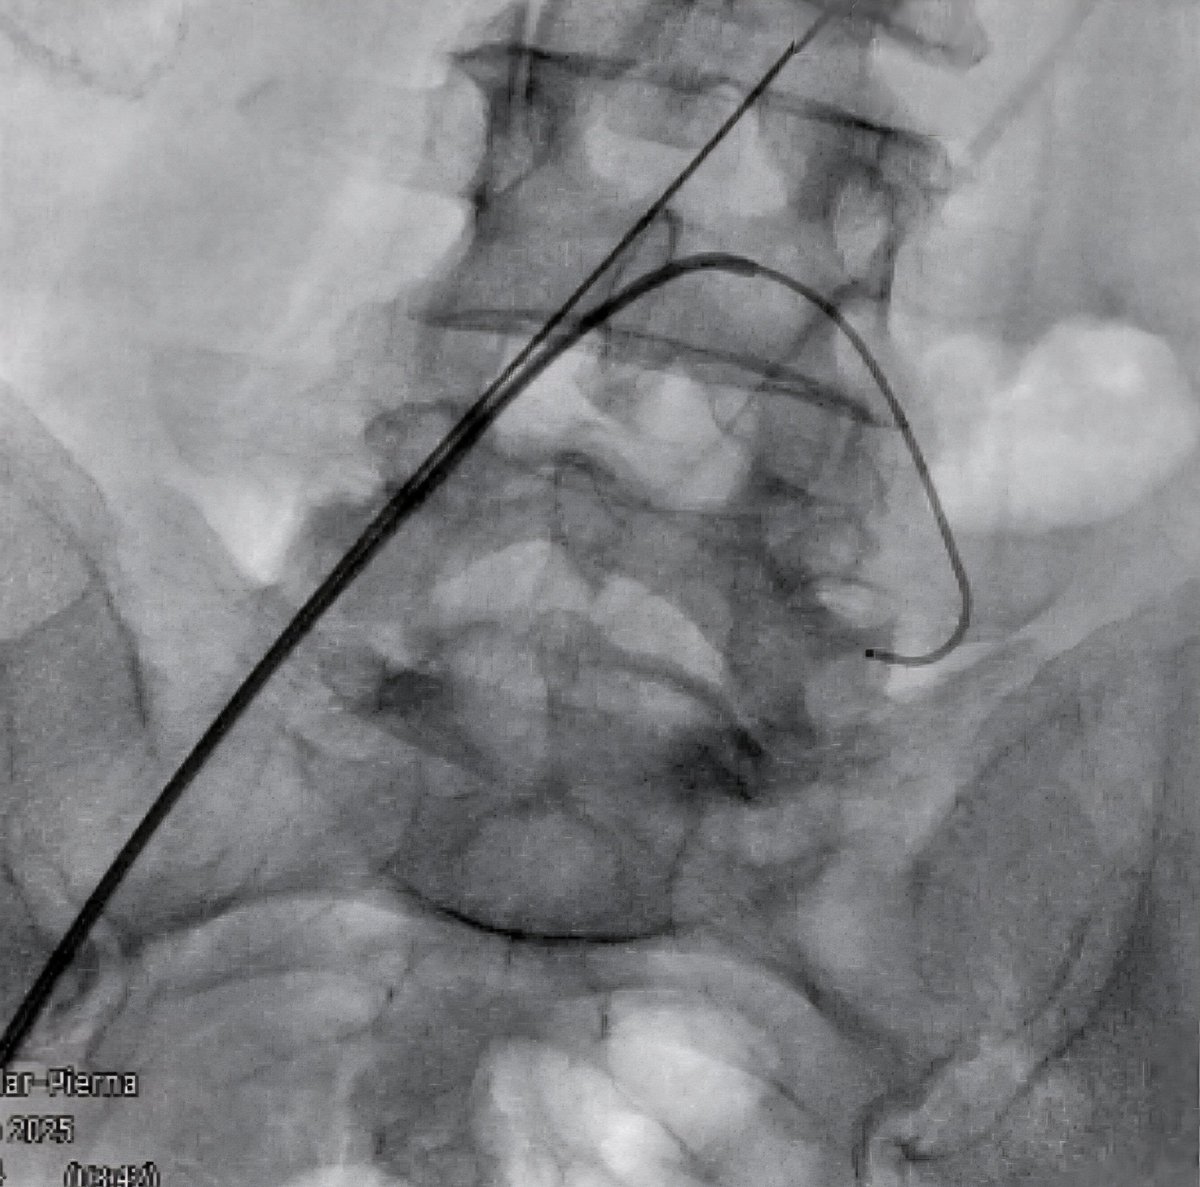

What better way to start holiday weekend call than a TIPS PR

Bleeding tips:

22 mins from lido to pressure, single stick w/ #ScorpionX

Gradient 27>8mmHg, 8cm Viatorr

#ICETIPS @WLGore @ArgonMedical

Props again to @tarheeldylan and @_backtable (episode 455 for basic technique)